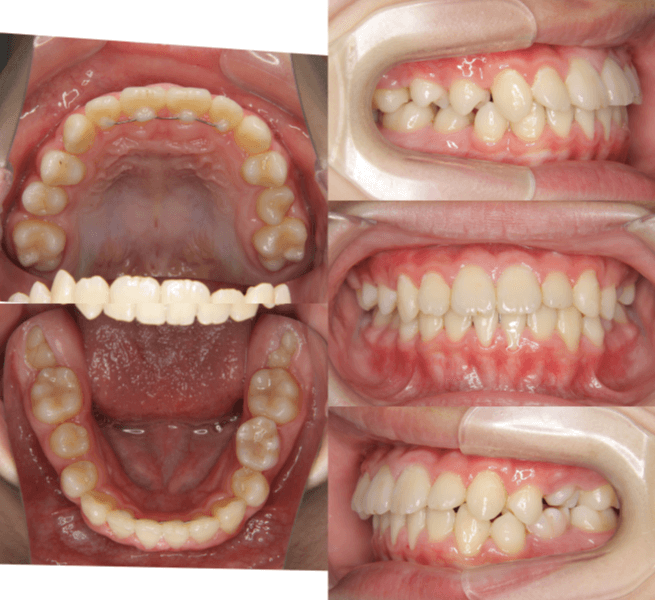

早期矯正治療 叢生症例①

主訴 | 歯の生えるスペース不足が懸念され、歯列の乱れ(叢生)を整えるために来院された患者様です。 |

---|---|

診断結果 | 7歳1か月の男児。 叢生の進行が見込まれると診断されました。 |

治療内容 |

|

治療後の経過 | 1年3か月の動的治療を通じて、上下顎の歯列が改善されました。 治療終了後は3〜4か月に一度の定期検診を継続しており、本格矯正治療の開始時期を判断していく方針です。 |

治療期間 | 動的治療期間:1年3か月 通院回数:11回 |

治療費用 | 420,000円(税別) |